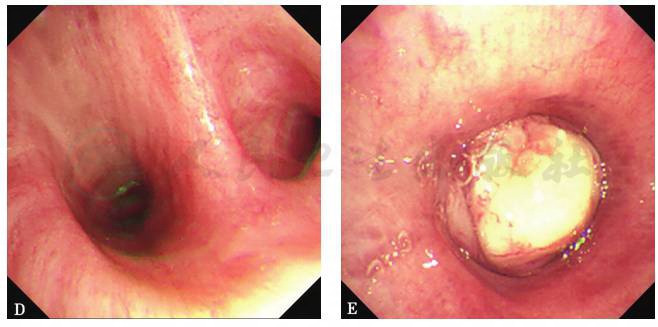

图11 支气管镜检查镜下表现

左主支气管远端见球形新生物,表面覆盖白色坏死物,管腔完全阻塞